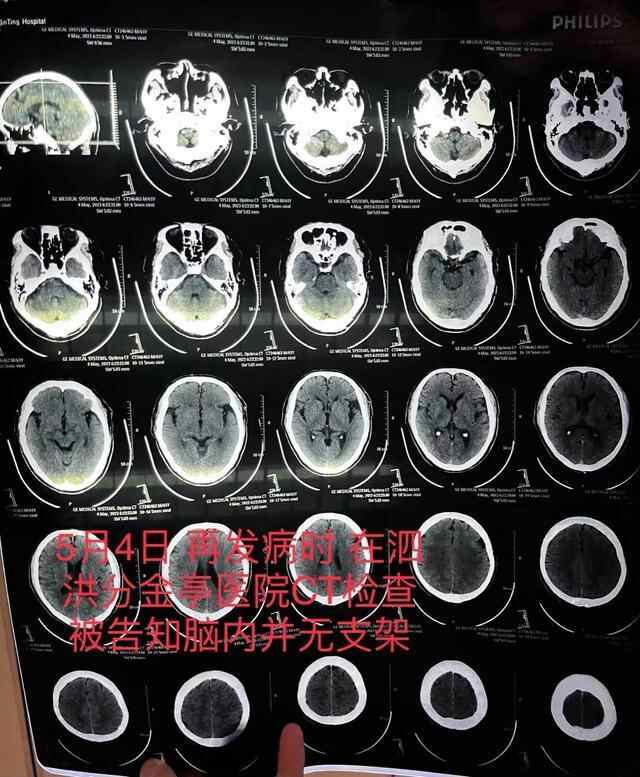

朱老汉的出院收费票据及部分明细。朱先生供图老人突然发病,医生承认支架植入失败5月4日,朱老汉突发严重脑梗。他先被救护车送至江苏省宿迁市泗洪县分金亭医院抢救。

令家属没想到的是,当时的CT检查发现,其颅内段部分动脉已严重堵闭,同时未发现此前植有支架。“我们当时不相信这个检查结果,认为这是小医院,可能检查不出来,所以我们决定转送到之前的医院。”朱先生说,朱老汉又被转入宿迁第一人民医院,曾作为主刀医生的齐某此时才承认,之前未能在患者颅内血管成功植入支架。